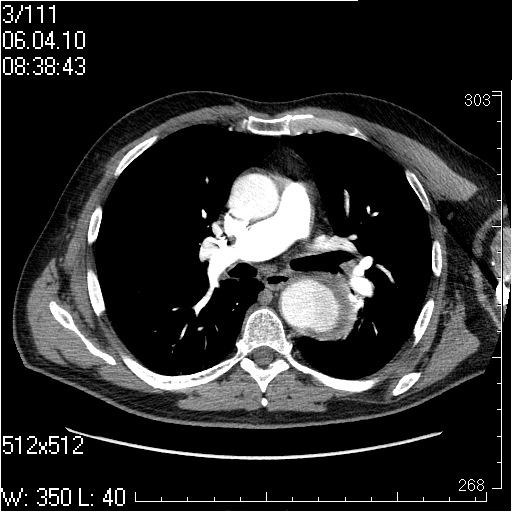

Грудной отдел аорты

Пожилой мужчина, жалоб в настоящее время не предъявляет.